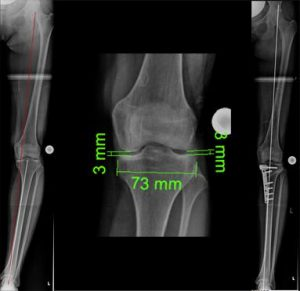

Beispiel einer aufklappenden Osteotomie, kniegelenksnah, am Schienbein bei O-Beinfehlstellung. Die MA wurde zentriert, da noch keine Schädigung des Gelenkes vorlag (Bild 2).

Zuklappende Osteotomie, kniegelenksnah, am Oberschenkel bei X-Bein (Bild 3).

Individualisierte Vorgehensweise beim O-Bein (Bild 4). Infolge einer Verletzung der kniegelenksnahen, innenseitigen Wachstumsfuge resultierte dort eine diskrete Beinverkürzung mit O-Beinfehlstellung. Durch das aufklappende Verfahren wurden sowohl Beinlänge wie –achse ausgeglichen.